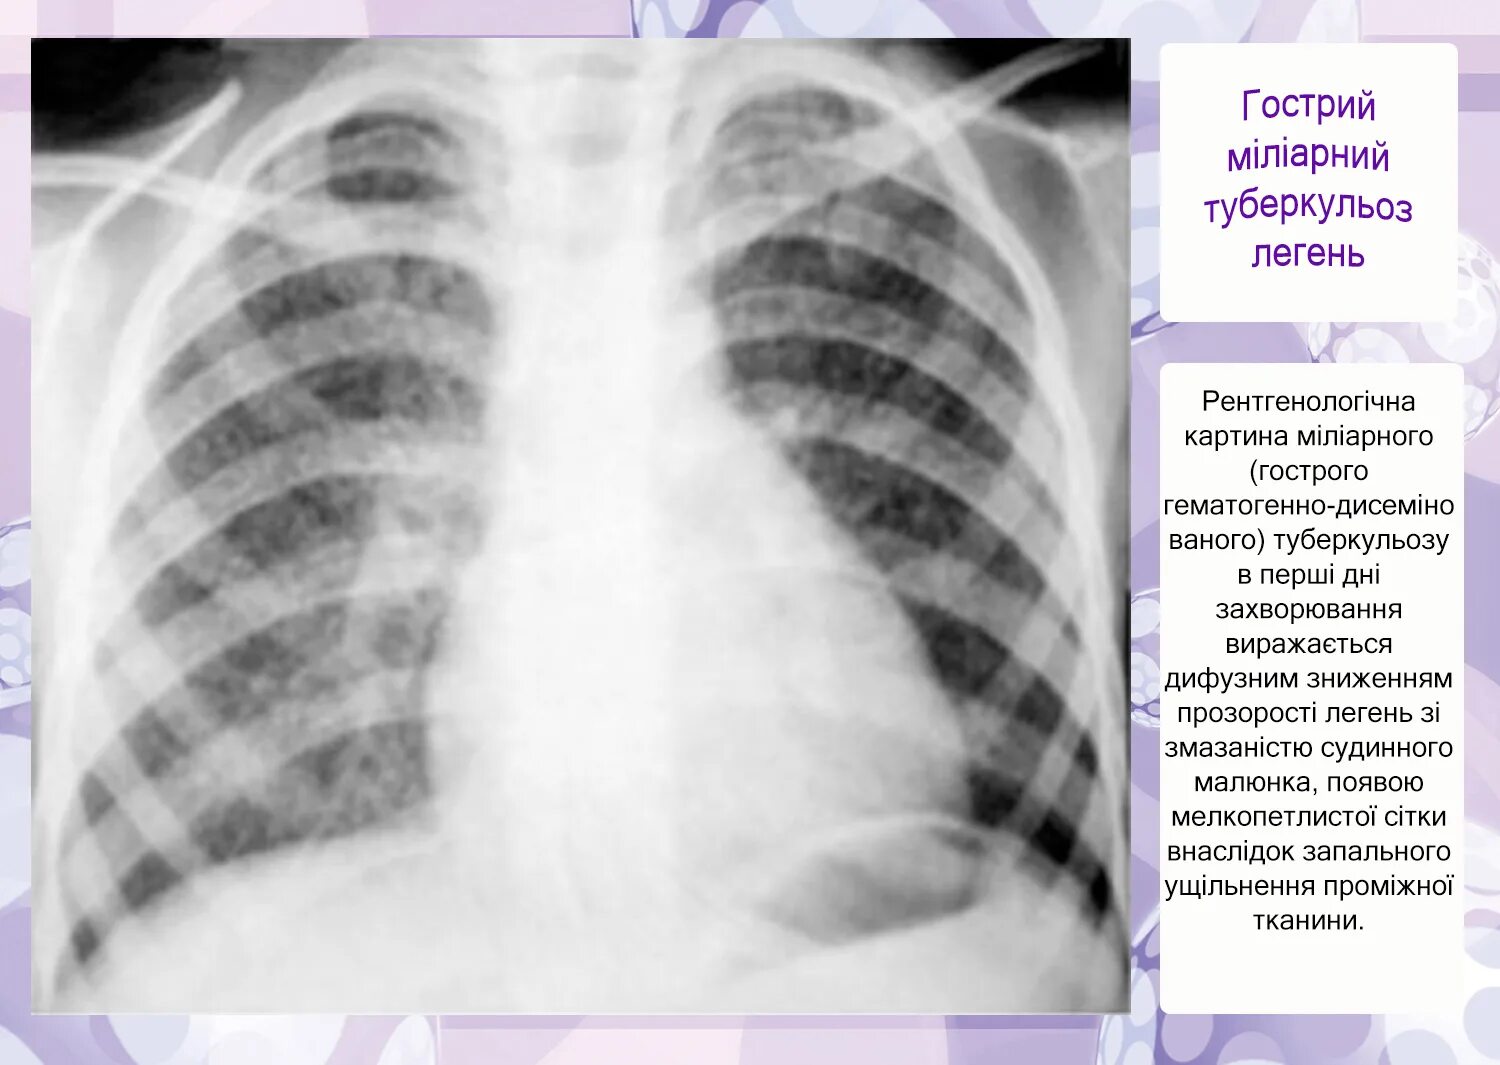

Метатуберкулезные изменения в легких что это означает